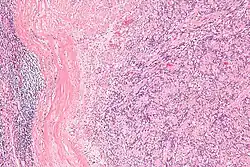

Low mag.

IPMs are diagnosed by examination of the tissue by a pathologist. They have a rim of peripheral lymphoid tissue (remnant of a lymph node) and consist of spindle cells with nuclear palisading. Red blood cell extravasation is common and blood vessels surrounded by collagen with (fine) peripheral spokes (amianthoid fibers) are usually seen.[2]

Immunostains for smooth muscle actin and cyclin D1 are characteristically positive. The main histologic differential diagnosis is schwannoma.